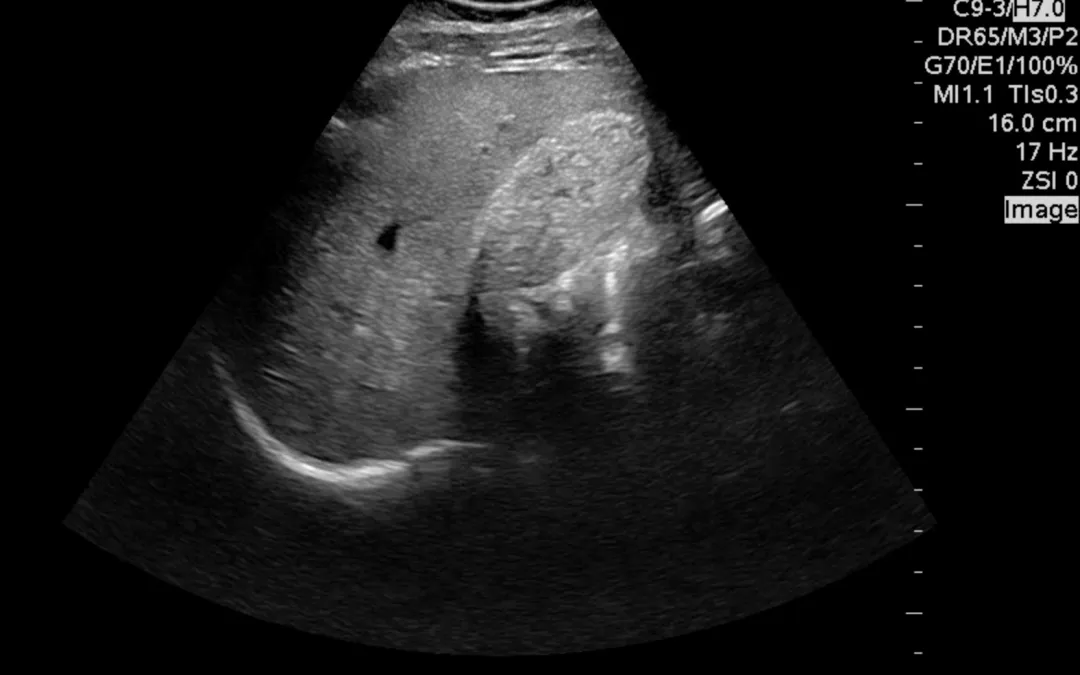

A 40-year-old male presented to the ED with 4 days of right upper quadrant pain. The pain came on acutely 4 days ago while eating and had been constant since then. He endorsed nausea, but denied vomiting, diarrhea, and fever. He had never had pain like this before....